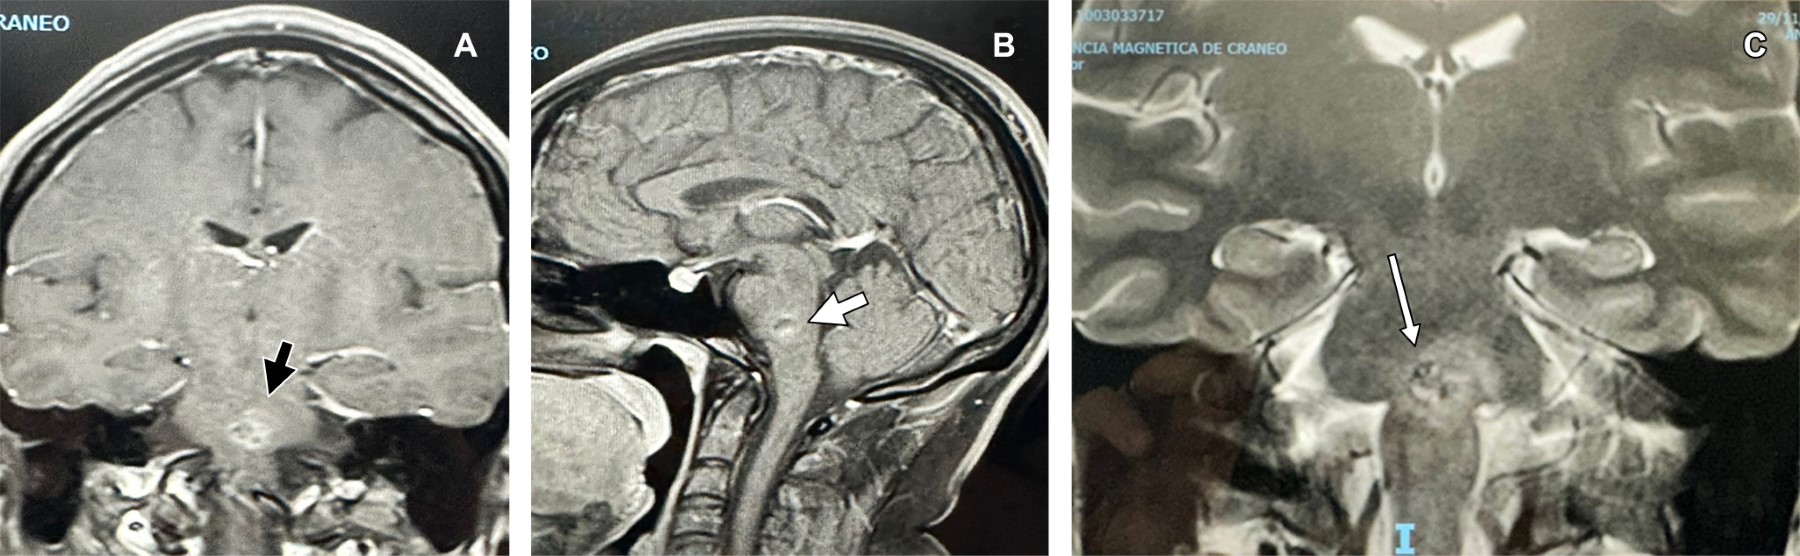

Femenino de 37 años que acudió por cervicalgia, se efectuó resonancia magnética cervical encontrando incidentalmente cavernoma asintomático en protuberancia (Figura 1); dos años después presentó sangrado del mismo (Figura 2), lo cual ocasionó termoanalgesia facial bilateral y del hemitórax derecho, parálisis ipsilateral de maseteros, ataxia, temblor y hemiparesia contralateral (síndrome de Grenet). Las malformaciones venosas cavernosas (MVC) cerebrales son denominadas actualmente "malformaciones venosas de flujo lento". Es la tercera malformación vascular cerebral más común, supratentoriales en ~80% de los casos. Las MVC del tronco encefálico son poco comunes (8 a 22%), de todos los cavernomas intracraneales 40% son hallazgos incidentales; su sintomatología en caso de sangrado es entre los 30 y 60 años, habitualmente son lesiones únicas. La mayoría permanecen asintomáticas. La presentación por hemorragia puede provocar cefalea, convulsiones o déficit neurológico focal. El riesgo de hemorragia es < 0.1 a 1% por paciente-año y de 5% en el tronco encefálico. Se componen de capilares hialinizados, dilatados, de paredes delgadas, rodeados de hemosiderina. La resonancia magnética es de elección diagnóstica, mostrando una apariencia característica de "palomitas de maíz" o "bayas" con pérdida del borde debido a hemosiderina. Las lesiones sintomáticas deben, cuando sea posible, resecarse y la resección completa es curativa.

Figura 2